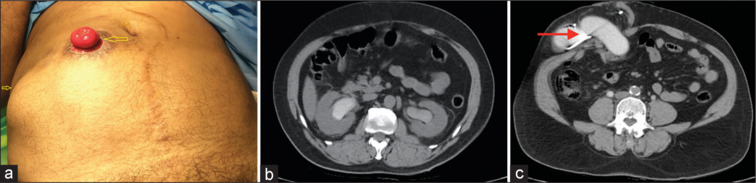

Conduit-related complications often occur late and are challenging to treat. A septuagenarian, 12 years following radical cystectomy and ileal conduit (IC) for T1G3 bladder cancer, presented with stomal stenosis which was managed by temporary placement of catheter into the conduit. One year later, he presented with no urine output from the conduit due to a double block resulting from a volvulus of the subcutaneous portion of the IC. After confirmation of the diagnosis with a computed tomography scan, the patient was managed by a reduction of the conduit length and a Turnbull stoma.